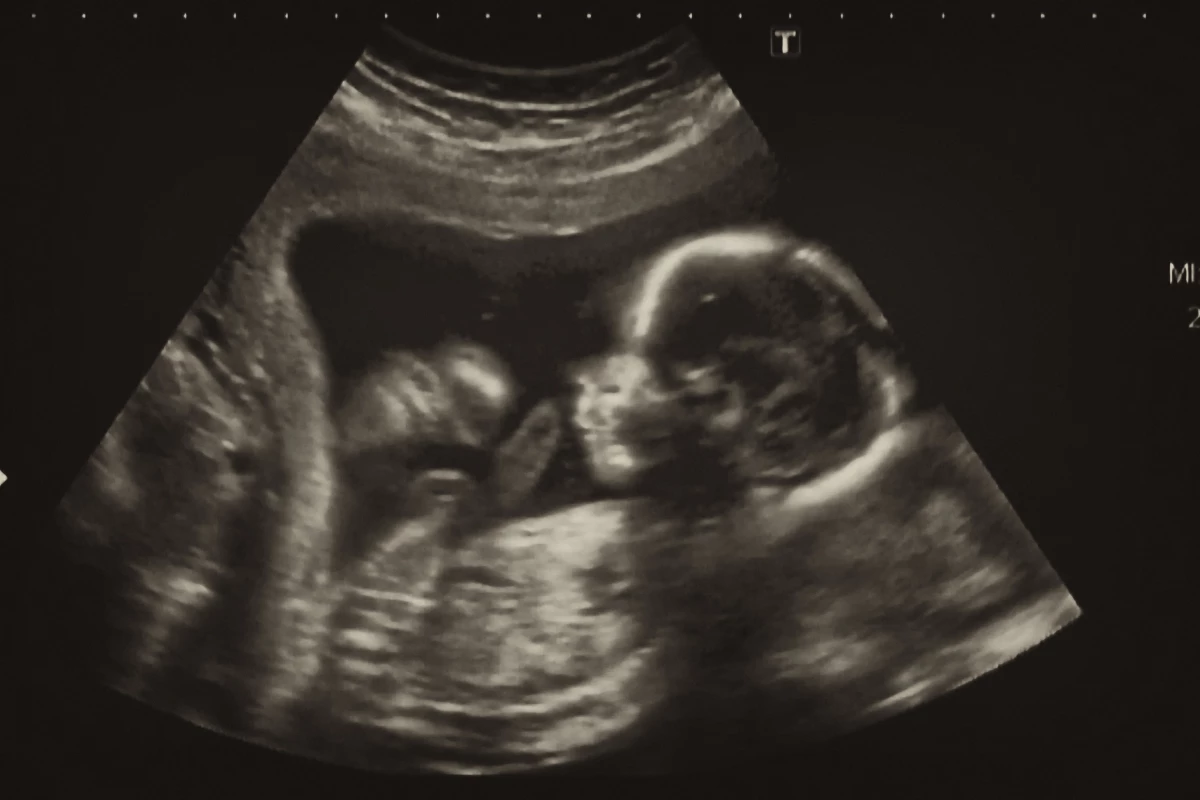

Surgeons have successfully performed a first-of-its-kind procedure in utero to treat a potentially fatal genetic defect in the brain. Usually treated after birth, the new procedure could give newborns a better chance of a normal life.

So for the first time, surgeons at Brigham and Women’s Hospital and Boston Children’s Hospital have now performed a VOGM embolization in utero, guided by ultrasound. While in the womb, placental circulation takes the stress off the fetus’ heart and brain, protecting them from damage. The hypothesis was that performing the procedure before birth could improve outcomes.

The team performed the procedure on a fetus at 34 weeks and two days gestation, and appears to have been successful. The baby was born in mid-March and MRI scans showed no signs of stroke, fluid buildup or hemorrhage, which are common symptoms of VOGM.